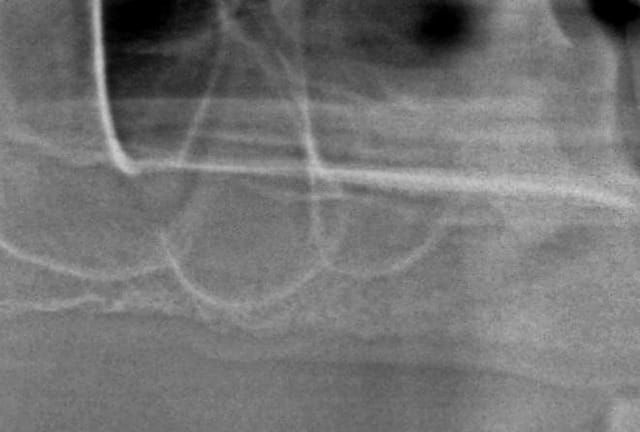

et la radio post op...

et pour le fun, ce que j'ai fait ce matin en 15min là aussi...

la patiente ne voulais pas faire de sinus lift car elle avait eu pas mal de pb de ce côté là...

donc, j'ai posé l'implant à raz le long du plancher sinusien

et bien, je souhaite bien du plaisir à qui doit poser un implant de la sorte à main levée en prenant à la fois en compte le sinus et l'émergence du col de l'implant pour ne pas avoir de pb pour faire la prothèse...

à part y aller millimètre par millimètre et prendre des radios à chaque fois....

P.S: j'ai quand même vérifié après l'insertion finale que je pouvais connecter un transfert...bilan, aucun problème!